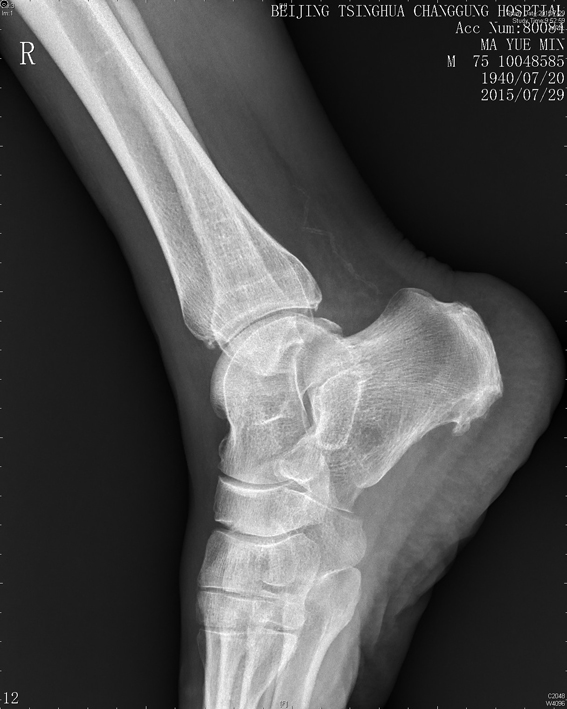

患者老年男性,主诉右侧踝部疼痛肿胀2年,加重10天。患者于2年前无明显诱因下出现右踝部疼痛肿胀,行走后加重,2年来症状反复发作,曾行封闭治疗后症状略缓解,近10天无诱因出现疼痛及肿胀较前加重,行走受限。查体:右侧踝关节疼痛肿胀,VAS评分7分,右下肢髂腰肌、股四头肌肌力V-级,余下肢肌力V级,踝关节活动范围正常。

右踝关节X线示:踝关节退行性变。

踝关节超声提示:右踝关节边缘可见少量骨质增生,外侧可见局部软组织水肿增厚。